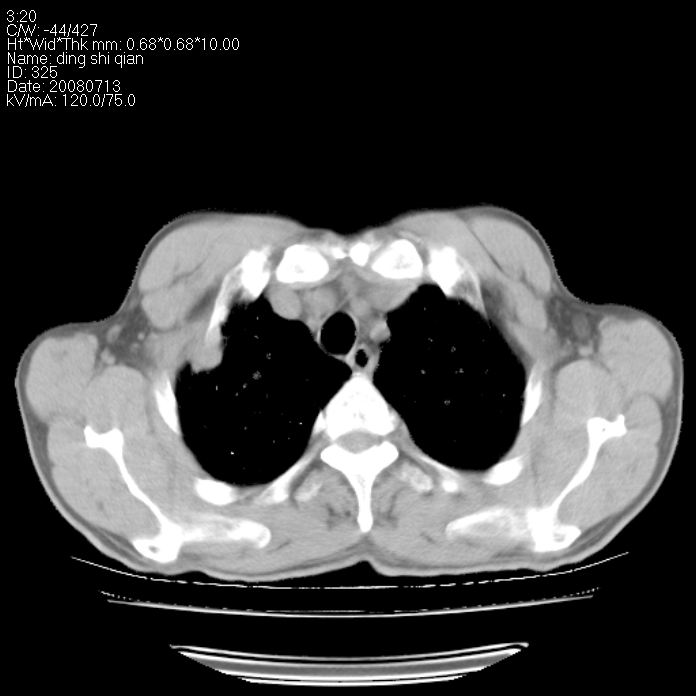

标题: CT14654:男 50岁 近来胸痛 [打印本页]

标题: CT14654:男 50岁 近来胸痛

右侧上肺块状软组织影,浅分叶,边缘毛刺证,与胸膜粘连,考虑:周围性肺癌

右肺上叶周围型肺癌可能性大。

右侧上肺块状软组织影,浅分叶,边缘毛刺证,与胸膜粘连,考虑:周围性肺癌!支持!

典型右肺周围型肺癌

右肺上叶周围型肺癌。